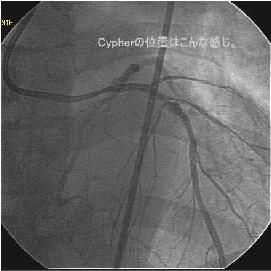

�ŏI�o���オ���IVUS�BIVUS��170507��septal���}����170509������2mm��O��

���̕����B

|

|

|

|